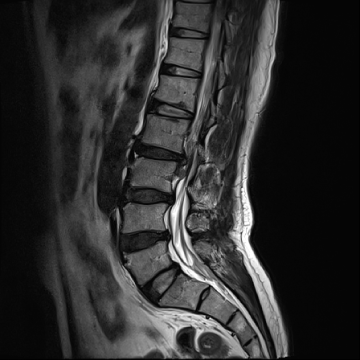

허리 디스크 수술 전·후

2021.10.19

2023.01.09

ㆍ환자 동의를 받은 자료이며, 이미지 사진은 실물과 다를 수 있습니다.

ㆍ모든 자료는 새움병원 자료입니다.